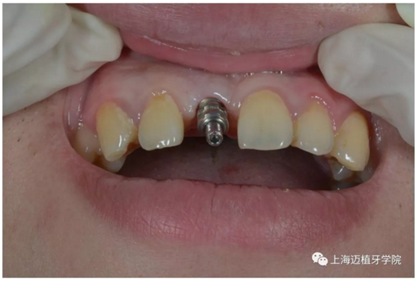

3月后恢復(fù)良好,上愈合基臺(tái)

2周后袖口成形